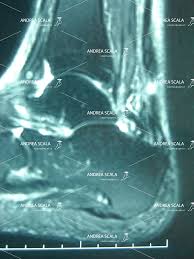

L'esame obiettivo è più sensibile della rm per la rilevazione di una rottura del tendine di achille ().uno studio su pazienti con una lesione del tendine di achille (2012) ha rilevato che se tutti e 3 i test (thompson, matles, palpazione del gap) sono positivi, la sensibilità per la lacerazione del tendine d'achille è del 100%. Questo trauma è molto più frequente negli uomini con un rapporti di 6 a 1 e la fascia d'età più colpita è fra i 35 e i 40 anni. Domani, come riportato da sky sport, il terzino dell' italia e della roma volerà in finlandia dal professor orava , il medico dei miracoli che nel 2019 riattaccò il tendine all. E' più grave del previsto l'infortunio di leonardo spinazzola, uscito anzitempo: Ferretti per gli esami al sant'andrea, che purtroppo non si è discostata dalla prima. Nella maggior parte dei casi, il processo flogistico si sviluppa in seguito a microtraumi ripetuti ed alterazioni di carattere degenerativo che, nel corso. Rottura del tendine d'achille confermate le anticipazioni della vigilia: Possono sembrare dei dati anedottici, che si dimenticano poco dopo averli letti.

Nella maggior parte dei casi, il processo flogistico si sviluppa in seguito a microtraumi ripetuti ed alterazioni di carattere degenerativo che, nel corso. Videotestimonianza e curiosità sul tendine d'achille:giuseppe è uno dei tanti sportivi che ogni anno si rompono il tendine d'achille in un gesto banale come. «rottura del sottocutanea del tendine d'achille». Una rottura del tendine d'achille, comunque, può verificarsi anche in caso di: Attualmente, al trattamento incruento si preferisce quello chirurgico in quanto con il primo (che prevede l'applicazione di uno stivaletto con ' caviglia in equino' per consentire al tendine di rigenerarsi da solo) il rischio di una nuova rottura è alto. L'esame obiettivo è più sensibile della rm per la rilevazione di una rottura del tendine di achille ().uno studio su pazienti con una lesione del tendine di achille (2012) ha rilevato che se tutti e 3 i test (thompson, matles, palpazione del gap) sono positivi, la sensibilità per la lacerazione del tendine d'achille è del 100%. Questo trauma è molto più frequente negli uomini con un rapporti di 6 a 1 e la fascia d'età più colpita è fra i 35 e i 40 anni. Il primo a parlare di rottura del tendine d'achille fu ippocrate, che disse che questo tendine, se lesionato o rotto, causa febbre acuta, provoca soffocamento, delirio, e porta alla morte. Rottura tendine d'achille la cura la causa sembra esser legata ai microtraumi ripetuti che avvengono durate attività ad alto impatto come ad esempio il calcio , tennis , atletica , basket ed altre discipline simili. Spinazzola, confermata rottura del tendine d'achille. Questi possono includere antidolorifici o un gesso temporaneo per evitare che la gamba si muova. Aumento improvviso ed esagerato dei livelli di attività fisica. Se pensi di essere a rischio di una rottura del tuo tendine d'achille, qui ci sono alcune cose che puoi fare per contribuire a ridurre il rischio.